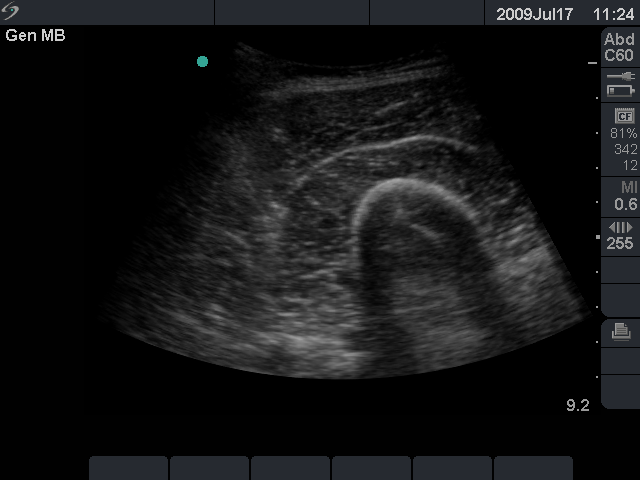

- On occasion, deeper structures need to be visualized; in these cases, a lower-frequency transducer is required. If a lower-frequency linear transducer is not available, then a curvilinear transducer may be used (Fig. 1).

- Figure 1. To image deep structures such as the thigh muscles, as shown here, a low-frequency curvilinear transducer may be used.